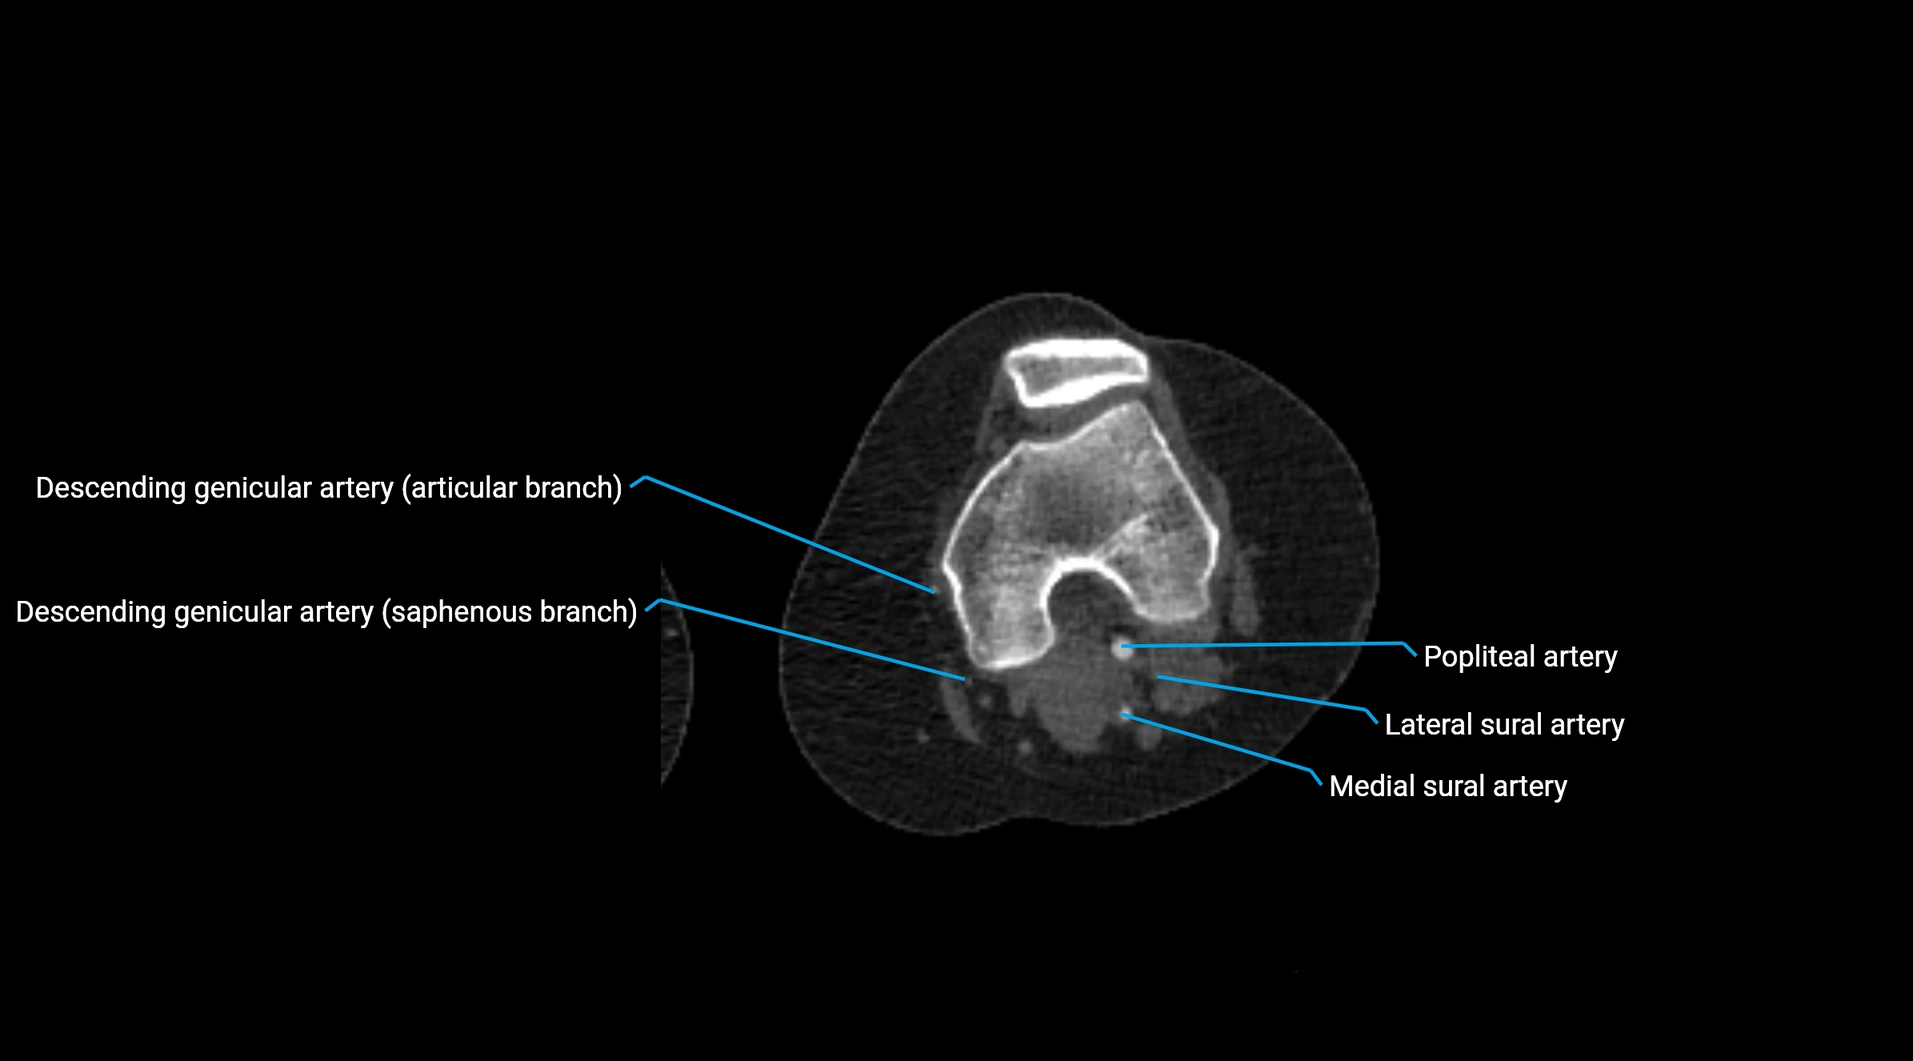

MRI images

image